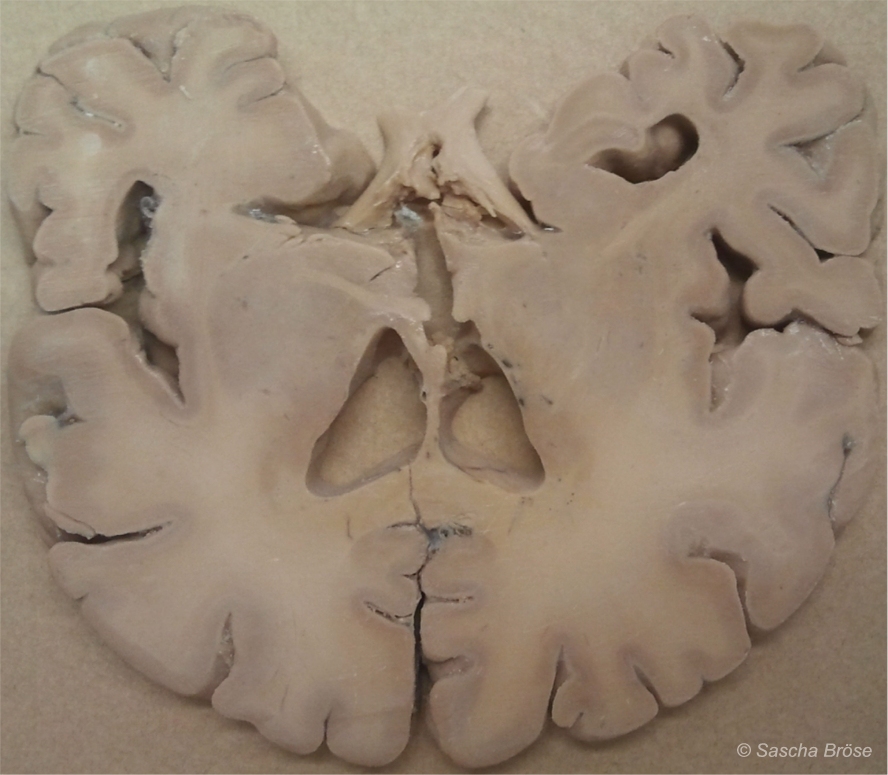

Aber wie sieht die Realität abseits vom Mythos des „komplexesten Gebildes des Universums“ aus? Betrachtet man Hirnpräparate, beispielsweise Hirngewebeschnitte, fällt die Uniformität der „grau-weißen Masse“ sofort auf (→ Abbildung 1). Die strukturelle Uniformität des Gehirngewebes steht im deutlichen Kontrast zu den hunderten Klassifikationen neurologisch‑psychiatrischer Erkrankungen. Es stellt sich doch sofort folgende Frage: Wie sollen so viele verschiedene Erkrankungen und Ursachenhypothesen plausibel sein, wenn das zugrunde liegende Gewebe in Aufbau und Funktion doch weitgehend uniform ist?

ABBILDUNG 1: EIN HIRNSCHNITT (LATERAL)

Abbildung 1: Ein Schnitt durch das menschliche Gehirn. Deutlich zu erkennen sind die Hirnwindungen mit den außenliegenden, grauen Bereichen der Nervenzellen. Zwar gibt es eine Menge verschiedener Subtypen von Nervenzellen, in Aufbau und Funktion sind sie grundsätzlich jedoch alle fast identisch. Davon zu unterscheiden ist die innere Substanz der Nervenleitungen (Axone) mit ihren myelinbildenden Gliazellen, die wesentlich heller ist und deshalb „weiße Substanz“ genannt wird. Verglichen mit anderen Organen, beispielsweise einer Niere oder einem Lungenflügel, sieht das zentrale Nervensystem klar strukturiert und geordnet aus, die zerfurchte Struktur entsteht nur aus Platzgründen, denn auf diese Weise konnte die Natur sehr viele Nerven- und Gliazellen auf kleinstem Raum unterbringen. Der ICD-10-Katalog unterscheidet in zwei Kapiteln dennoch knapp 200 Grobkategorien von Erkrankungen mit zahlreichen Unterkategorien, die fast alle das Gehirn betreffen. Sollte man daraus den Schluss ziehen, dass es auch ebenso zahlreiche Erkrankungsursachen auf der primären Organebene gibt? Die Uniformität des Gehirngewebes zeigt: Die Gründe können nur auf relativ wenigen grundsätzlichen Fehlfunktionen beruhen, so dass auch die unterschiedlichen Hirnregionen ausschlaggebend sein müssen, welche Symptome sich manifestieren. Das ist vergleichbar mit einem Multiplikatoreffekt, der leider unzählige Erkrankungsursachen auf der (primären) Organebene suggeriert, die es aber nicht gibt. So gerät man schnell auf eine falsche Fährte.